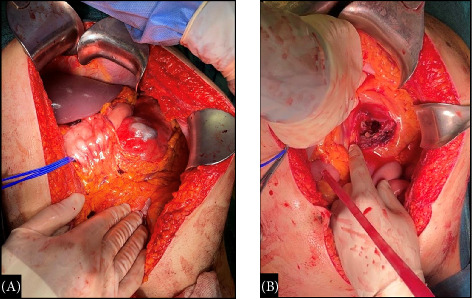

Background: Resuscitative endovascular balloon occlusion of the aorta (REBOA) is a technique aimed at temporarily interrupting or limiting blood flow through the aorta, which may be used as a bridge until definitive bleeding control by endovascular procedures or surgery. Despite the main current indication for its use is traumatic massive noncompressible torso hemorrhage, its application in end-stage nontraumatic abdominal and pelvic hemorrhage is progressively increasing. Case Presentation: A 42 year-old male patient was brought to our hospital Emergency Department with acute onset of abdominal pain, hypotension, paleness, and diaphoresis. A computed tomography (CT) was performed evidencing a voluminous retroperitoneal hematoma caused by the rupture of an unknown splenic aneurysm. Emergency open splenectomy with resection of the splenic aneurysm and evacuation of the retroperitoneal hematoma was performed, with the assistance of the REBOA technique. The endovascular balloon was positioned in the aorta, proximally to the celiac axis (Zone 1), through a percutaneous femoral access by the interventional radiologist. Intermittent aortic occlusion enabled proximal bleeding control, adequate myocardial and cerebral perfusion, and allowed surgeons to safely and successfully perform splenectomy by resecting the splenic artery at the origin. Conclusion: REBOA provides a rapid and minimally invasive hemodynamic control in severe hemorrhagic settings and its application in the initial management of nontraumatic abdominal hemorrhage should be strongly advised. Further studies with large sample size focusing on nontrauma patients are needed.